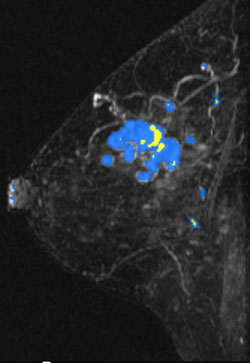

MR Angiomap

A right breast invasive lobular cancer (Estrogen Receptor/Progesterone Receptor +, Her-2 neu -).

Ultrasound demonstrates a dominant spiculated and irregular hypoechoic mass

Ultrasound demonstrates a dominant spiculated and irregular hypoechoic mass with dense posterior shadowing (known cancer). There were adjacent, similar-appearing hypoechoic irregular, spiculated masses present also.

MIP (Maximum Intensity Projection) image of MR

MIP (Maximum Intensity Projection) image of MR shows the known cancer: irregularly marginated mass in the upper outer to central breast. Satellite subcentimeter nodules are present anteromedially and posteriorly.